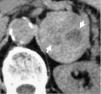

Diagnóstico de feocromocitoma mediante tomografía computarizada

Diagnosis of pheochromocytoma by computed tomography

E. Vázquez Muñoz, M. Atienza Saura, F.J. Barbado Hernández, M. López Rodríguez

Servicios de Radiodiagnóstico y de Medicina Interna. Hospital Universitario La Paz. Madrid. España